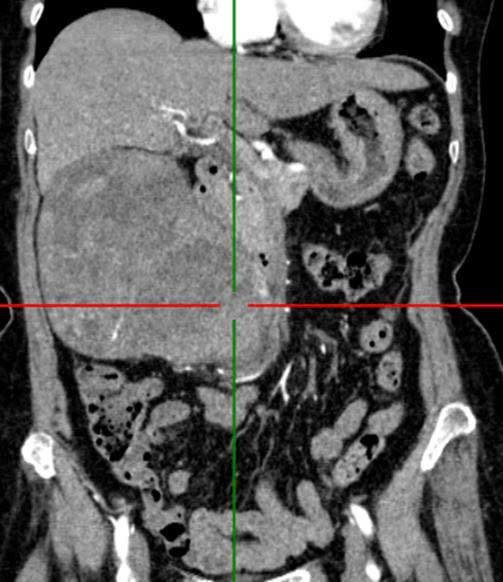

Khối u thận kích thước lớn trên phim chụp - Ảnh BVCC

Người bệnh nữ 72 tuổi nhập viện vì đau âm ỉ vùng hông lưng phải kéo nhiều tháng nay. Khám lâm sàng: Bệnh nhân tỉnh, đau tức nhiều vùng mạn sườn phải, vùng mạn sườn phải, thắt lưng phải có khối, ấn căng tức, mật độ chắc, ranh giới không rõ, PUTB (-), CUPM (-), nước tiểu trong.

Cận lâm sàng: Cắt lớp vi tính bụng (1-32 dãy có thuốc): Thận phải: To, nhu mô không đều, có hình ảnh khối choán chỗ ngấm thuốc mạnh sau tiêm, KT (118 x 133 x 135)mm. Đài bể thận giãn, không thấy sỏi. Kết luận u thận phải.